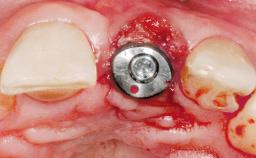

Immediate Placement of an Implant in a Maxillary Left Central Incisor Site

A 33-year-old female patient presented with an upper left central incisor that required extraction after a failed endodontic therapy. The tooth had been traumatized when the patient was a teenager and had undergone several endodontic treatments, including two apicectomy procedures. The patient was in good health and did not smoke. Clinical examination showed that the patient had a high lip line. In full smile, the gingival margins of the upper teeth were visible to the first molars. The gingival margins of central incisors 11 and 21 were only just showing. Examination of tooth 21 confirmed that the tooth was mobile and had hypererupted by 1 mm.

Type of Implants One-Piece

Placement Protocol Immediate implant placement

Tooth Site Maxillary incisor or canine

Socket Morphology Single-root socket